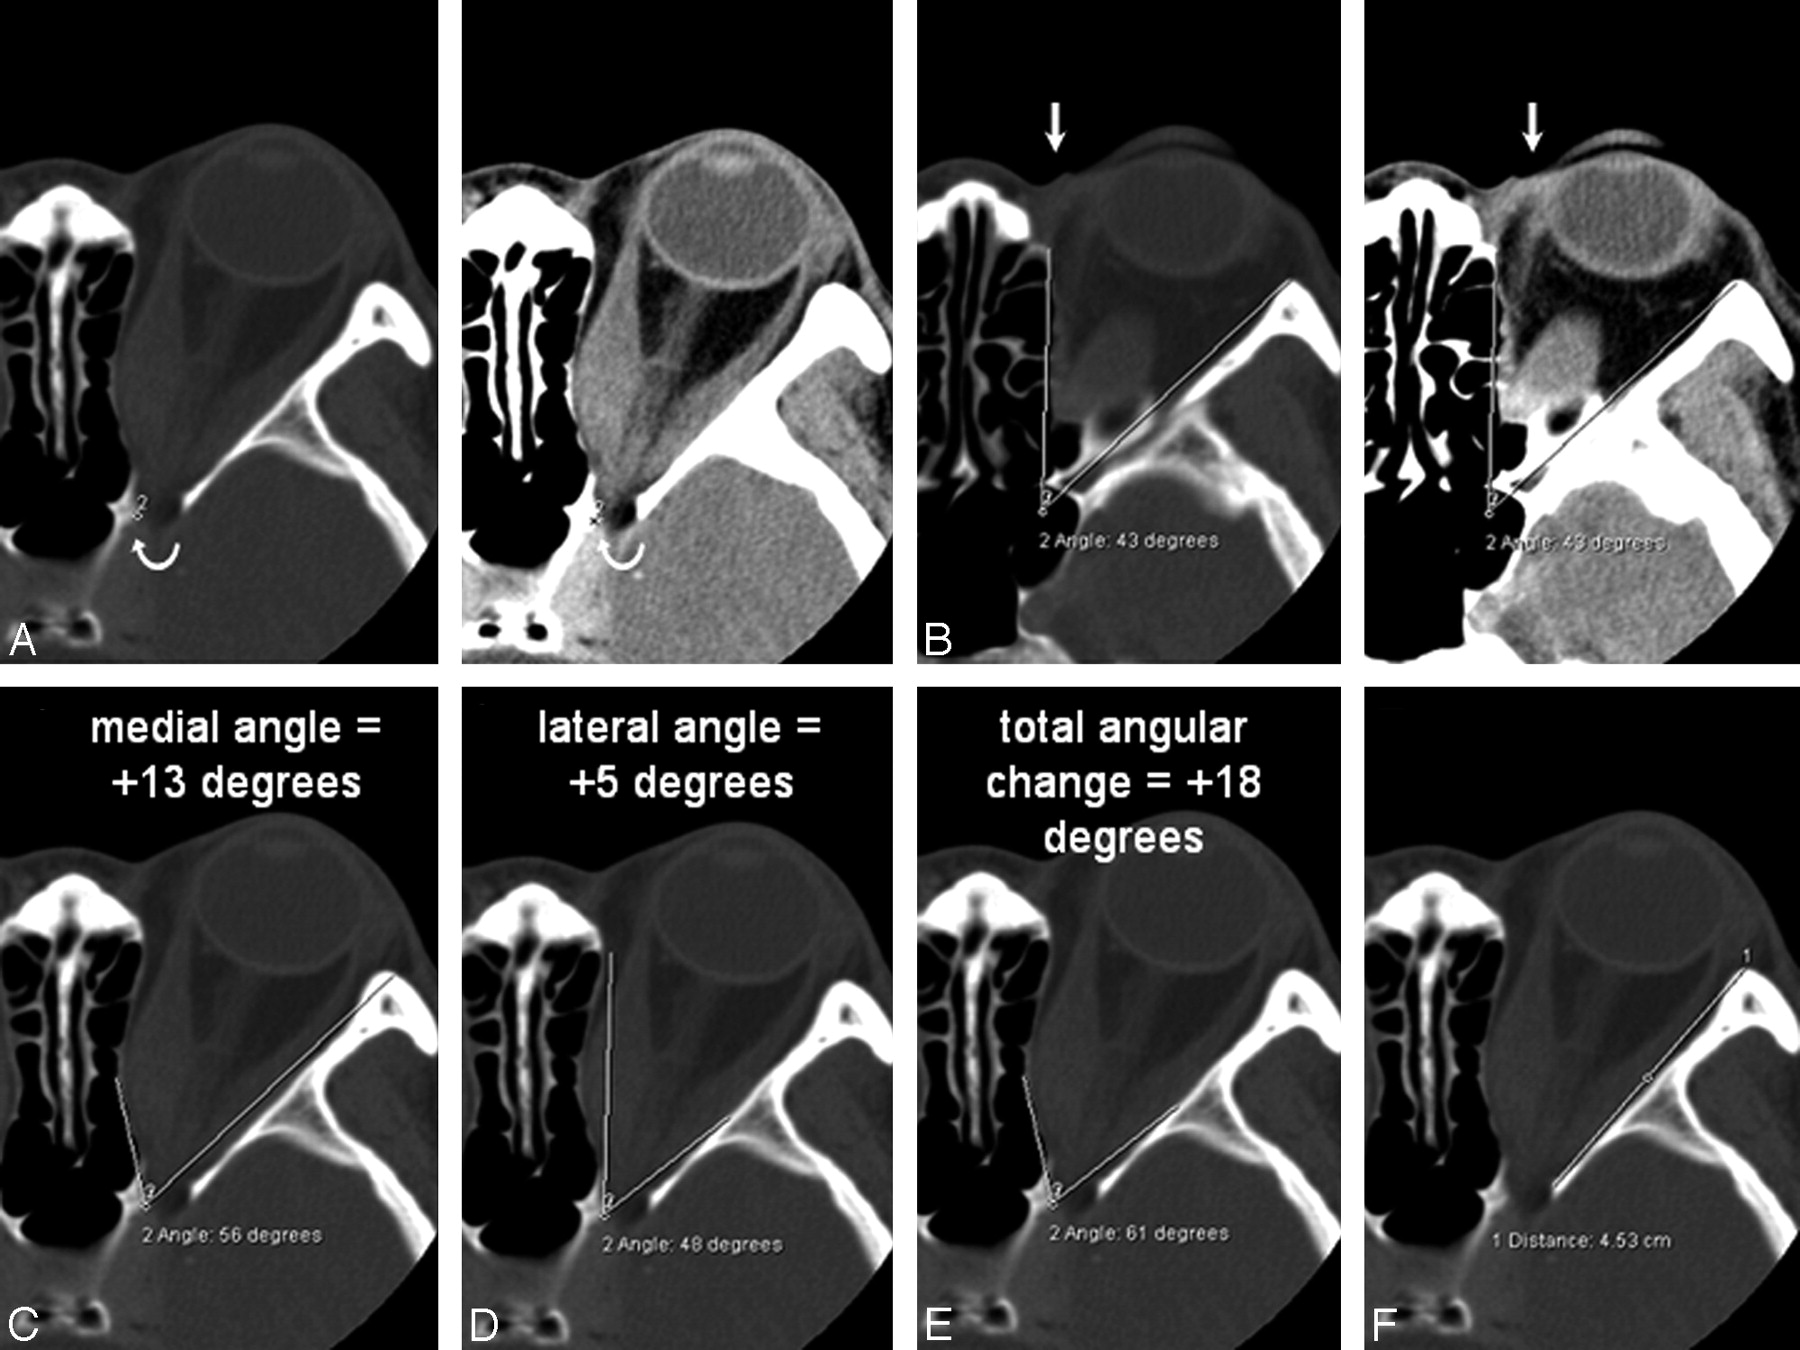

The capacity of the bony apex was quantified by using standardized orbital angles on axial scans. The orbital apex was defined as the anterolateral border of the groove in the sphenoid body formed by the terminal intracavernous portion of the internal carotid artery (Fig 1A). This apex point was electronically copied onto the series. The orbital rim angle was measured on the section containing the medial palpebral ligament (Fig 1B). This angle was used as a reference and was also electronically copied onto the series. The medial and lateral orbital wall angles (Fig 1C, -D) were measured as angular changes with respect to the orbital rim angle on the image containing the widest diameter of the medial and lateral rectus muscles. The angle that best described the widest bony point of the orbital wall around the muscular bellies was recorded. The angular change was recorded as positive if the resultant angle was wider than the orbital rim angle and negative for narrower angles. The total angular change was computed by the sum of the medial and lateral wall angles. The actual orbital apex angle (Fig 1E), as subtended by the medial and lateral orbital walls, was also recorded. The length of the lateral orbital wall was measured from the lateral border of the superior ophthalmic fissure to the orbital rim (Fig 1F).

A and B, Axial CT scans (bone window on left, soft tissue window on right) showing the orbital apex point indicated by the curved arrow (A) and the orbital rim angle (B). A, The apex point is defined as the anterolateral border of the groove in the sphenoid body formed by the intracavernous portion of the internal carotid artery (labeled 2) on the section just inferior to the anterior clinoid process. B, The orbital rim angle (43°) is measured at the level of the medial palpebral ligament (arrow). C−E, The same axial section containing the bulk of the medial and lateral rectus muscles shows the medial wall angle (C), the lateral wall angle (D), and the orbital apex angle (E). For the medial and lateral walls, the angle that best describes the widest bony point of the orbital wall around the muscular bellies is recorded. The angular change is recorded as positive if the resultant angle is wider than the orbital rim angle, and negative for narrower angles. F, The length of the lateral orbital wall is measured on the section just inferior to the anterior clinoid.